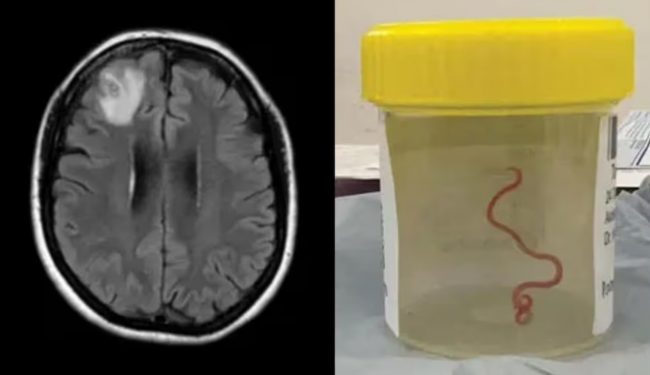

महिलाको मस्तिष्कमा भेटियो जिउँदो कीरा, विश्वकै पहिलो केस, डाक्टर पनि चकित